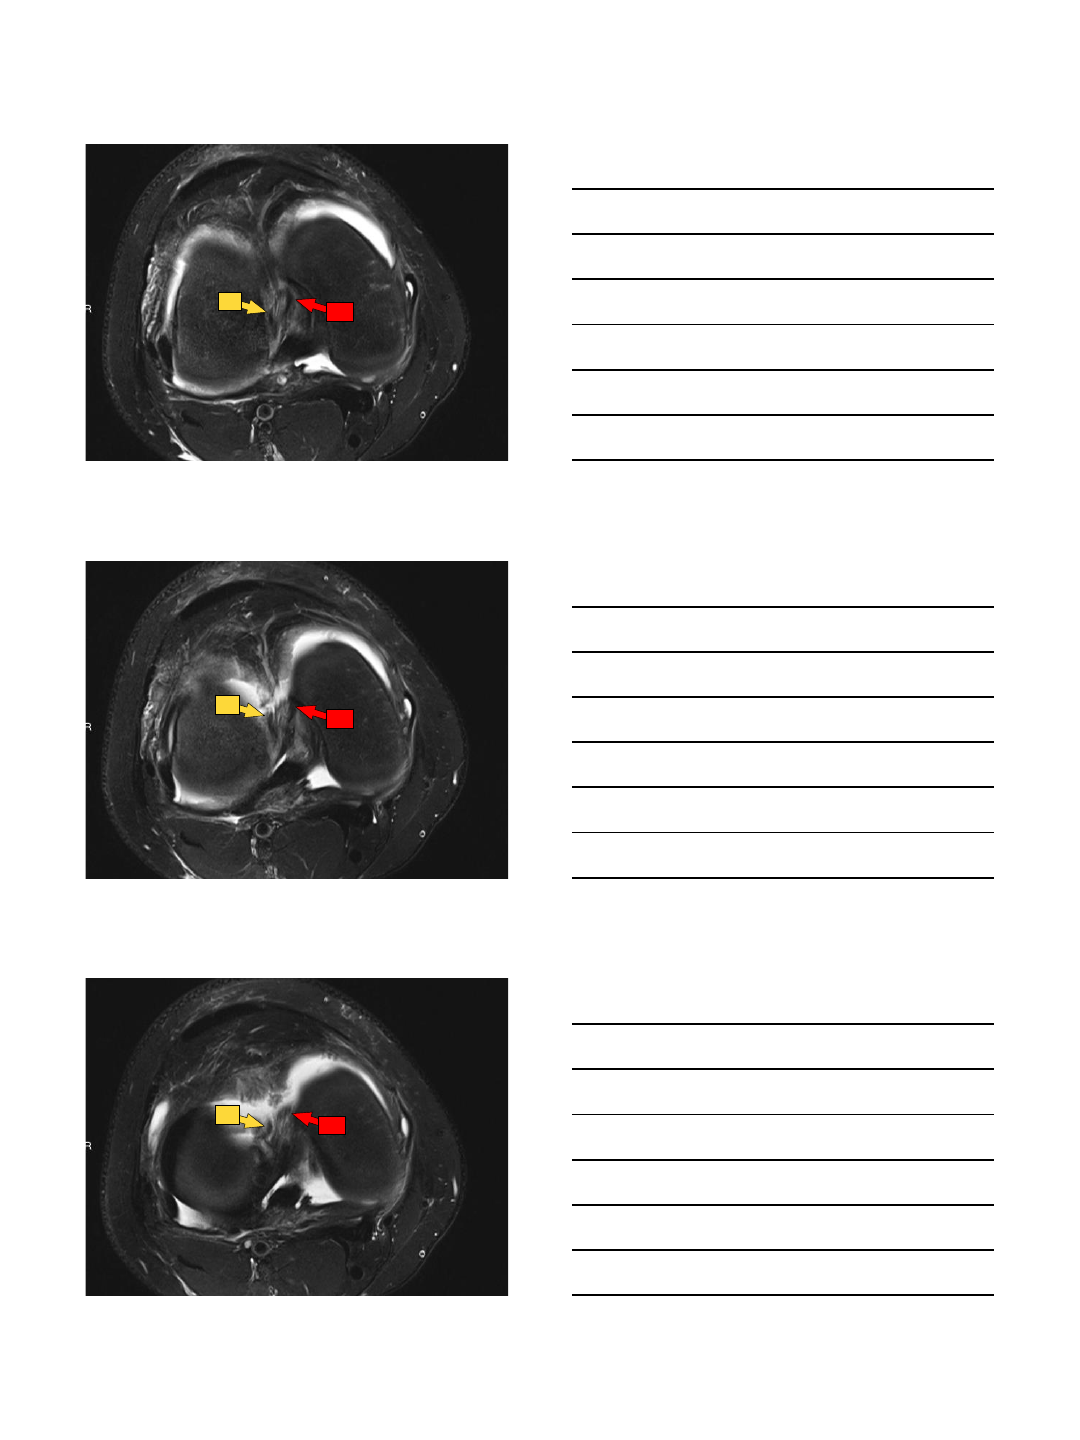

Bucket handle

•Circumferential longitudinal vertical tear

w/ displacement of free internal fragment

into intercondylar notch

•MM > LM

•MRI Signs

–Double PCL

–Double delta (lateral)

–Large AH

–Fragment in notch

–Absent bow tie

–Disproportionate horns

Double PCL

Double delta

Large AH

48 year-old man with medial knee pain.

Twisting injury a few months ago, heard a

“crack”.

10/13/2015